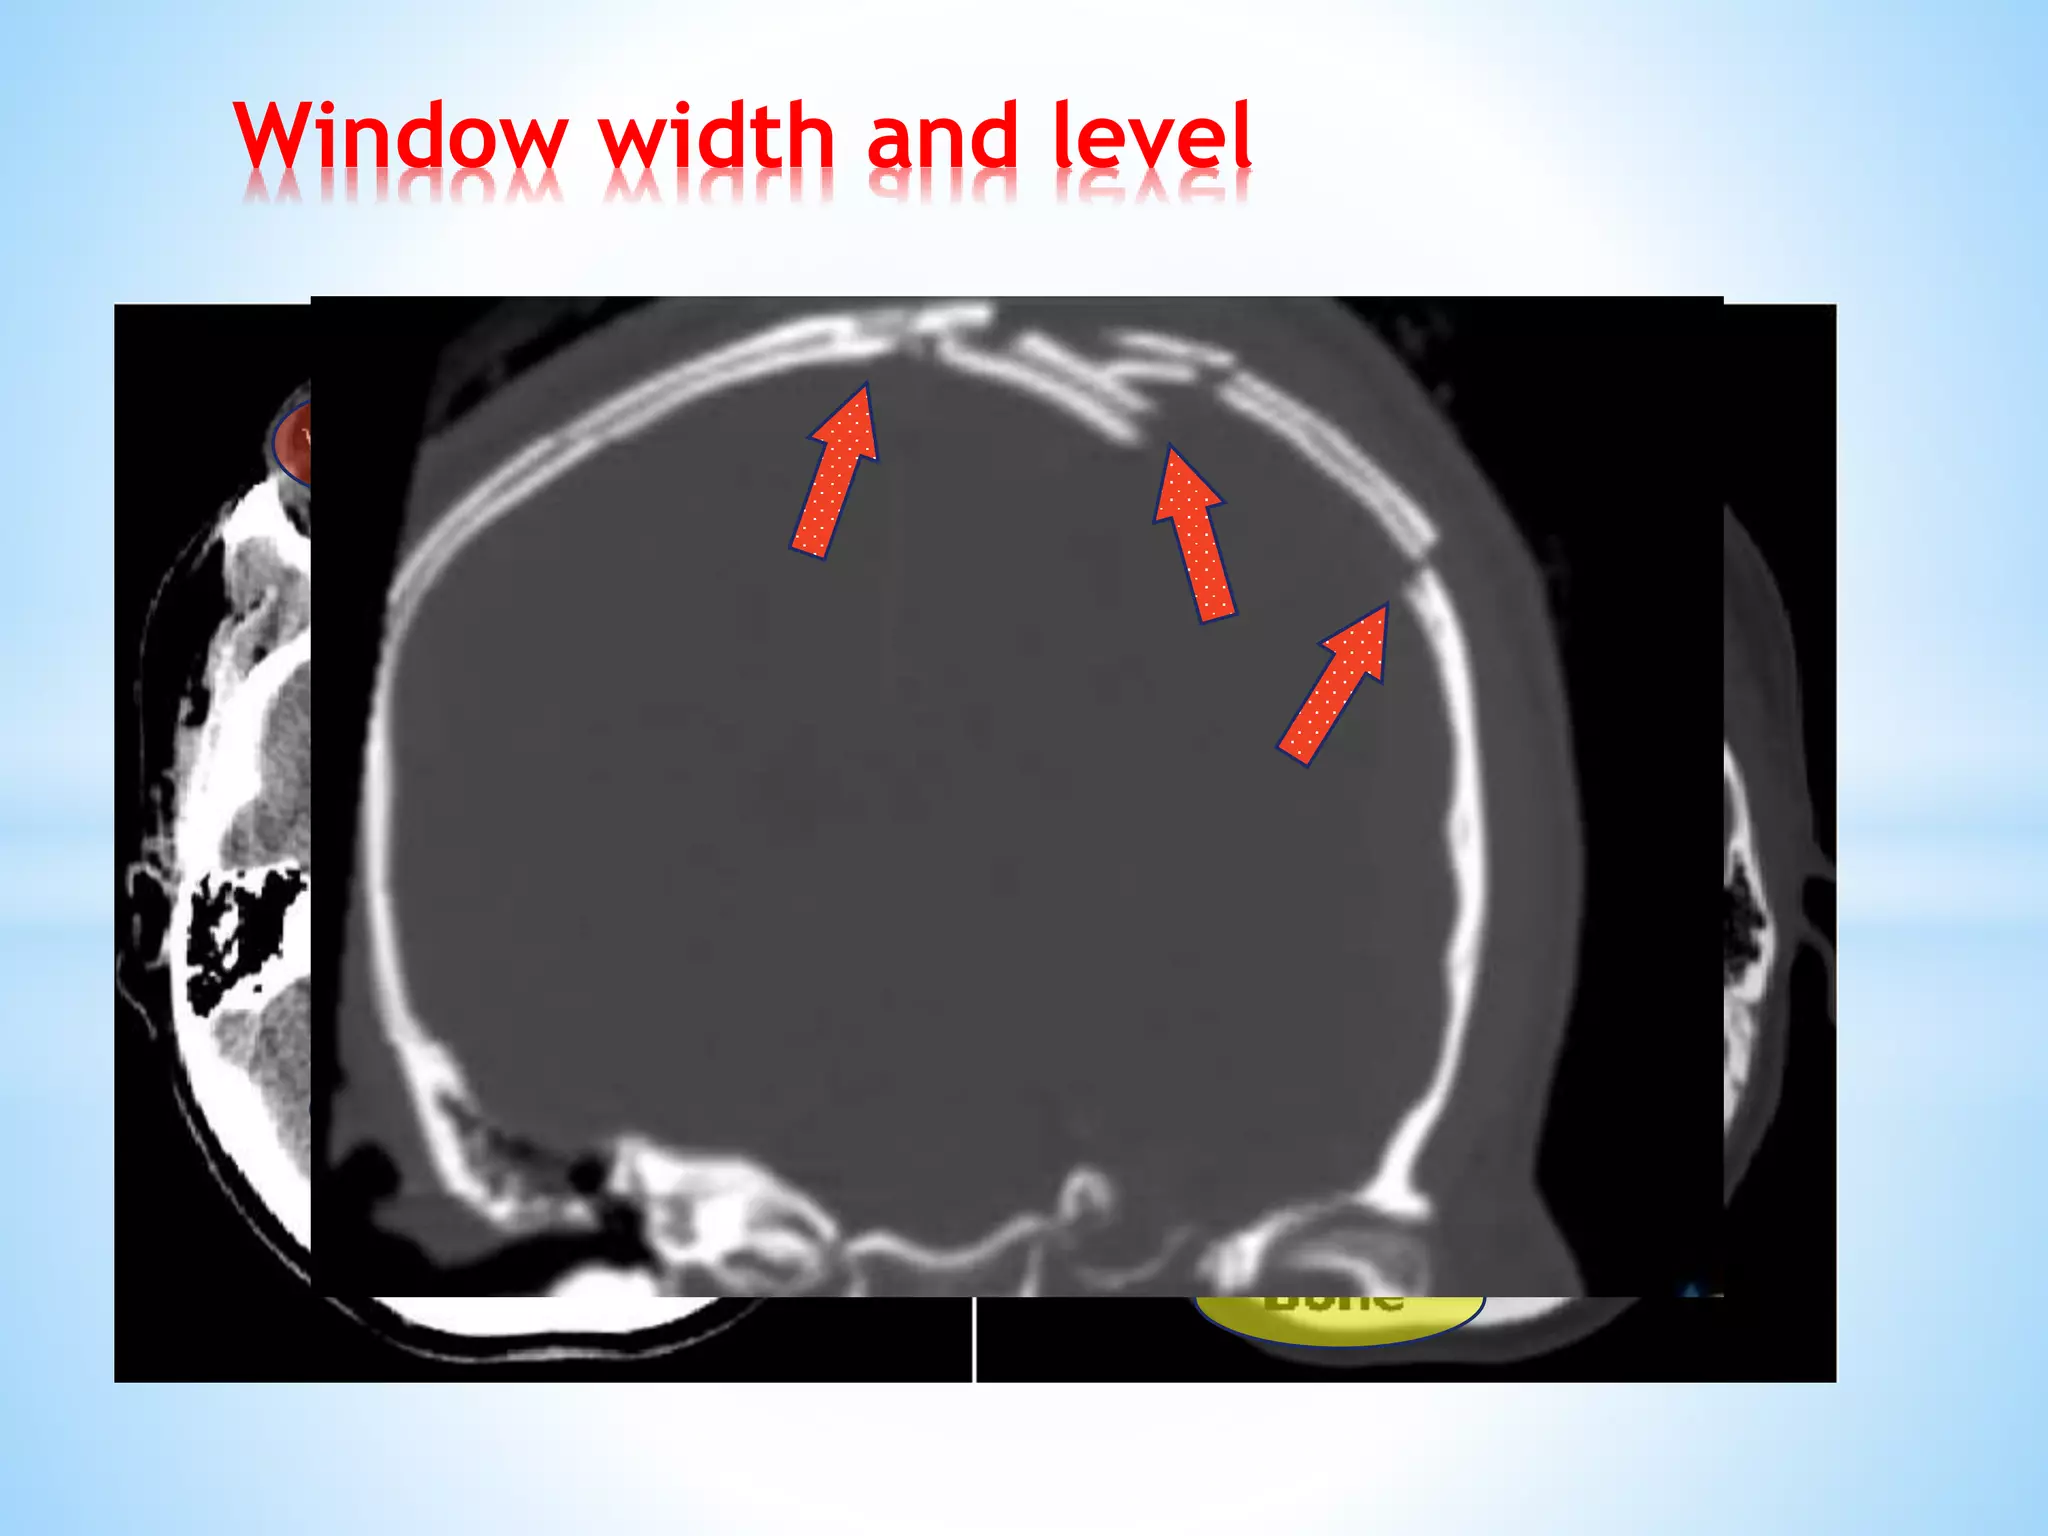

Window width and level

It is process of using the calculated Hounsfield Unites(HU), to make interpretable CT

images.

Window width andlevel It is process of using the calculated Hounsfield Unites(HU), to make interpretable CT images.